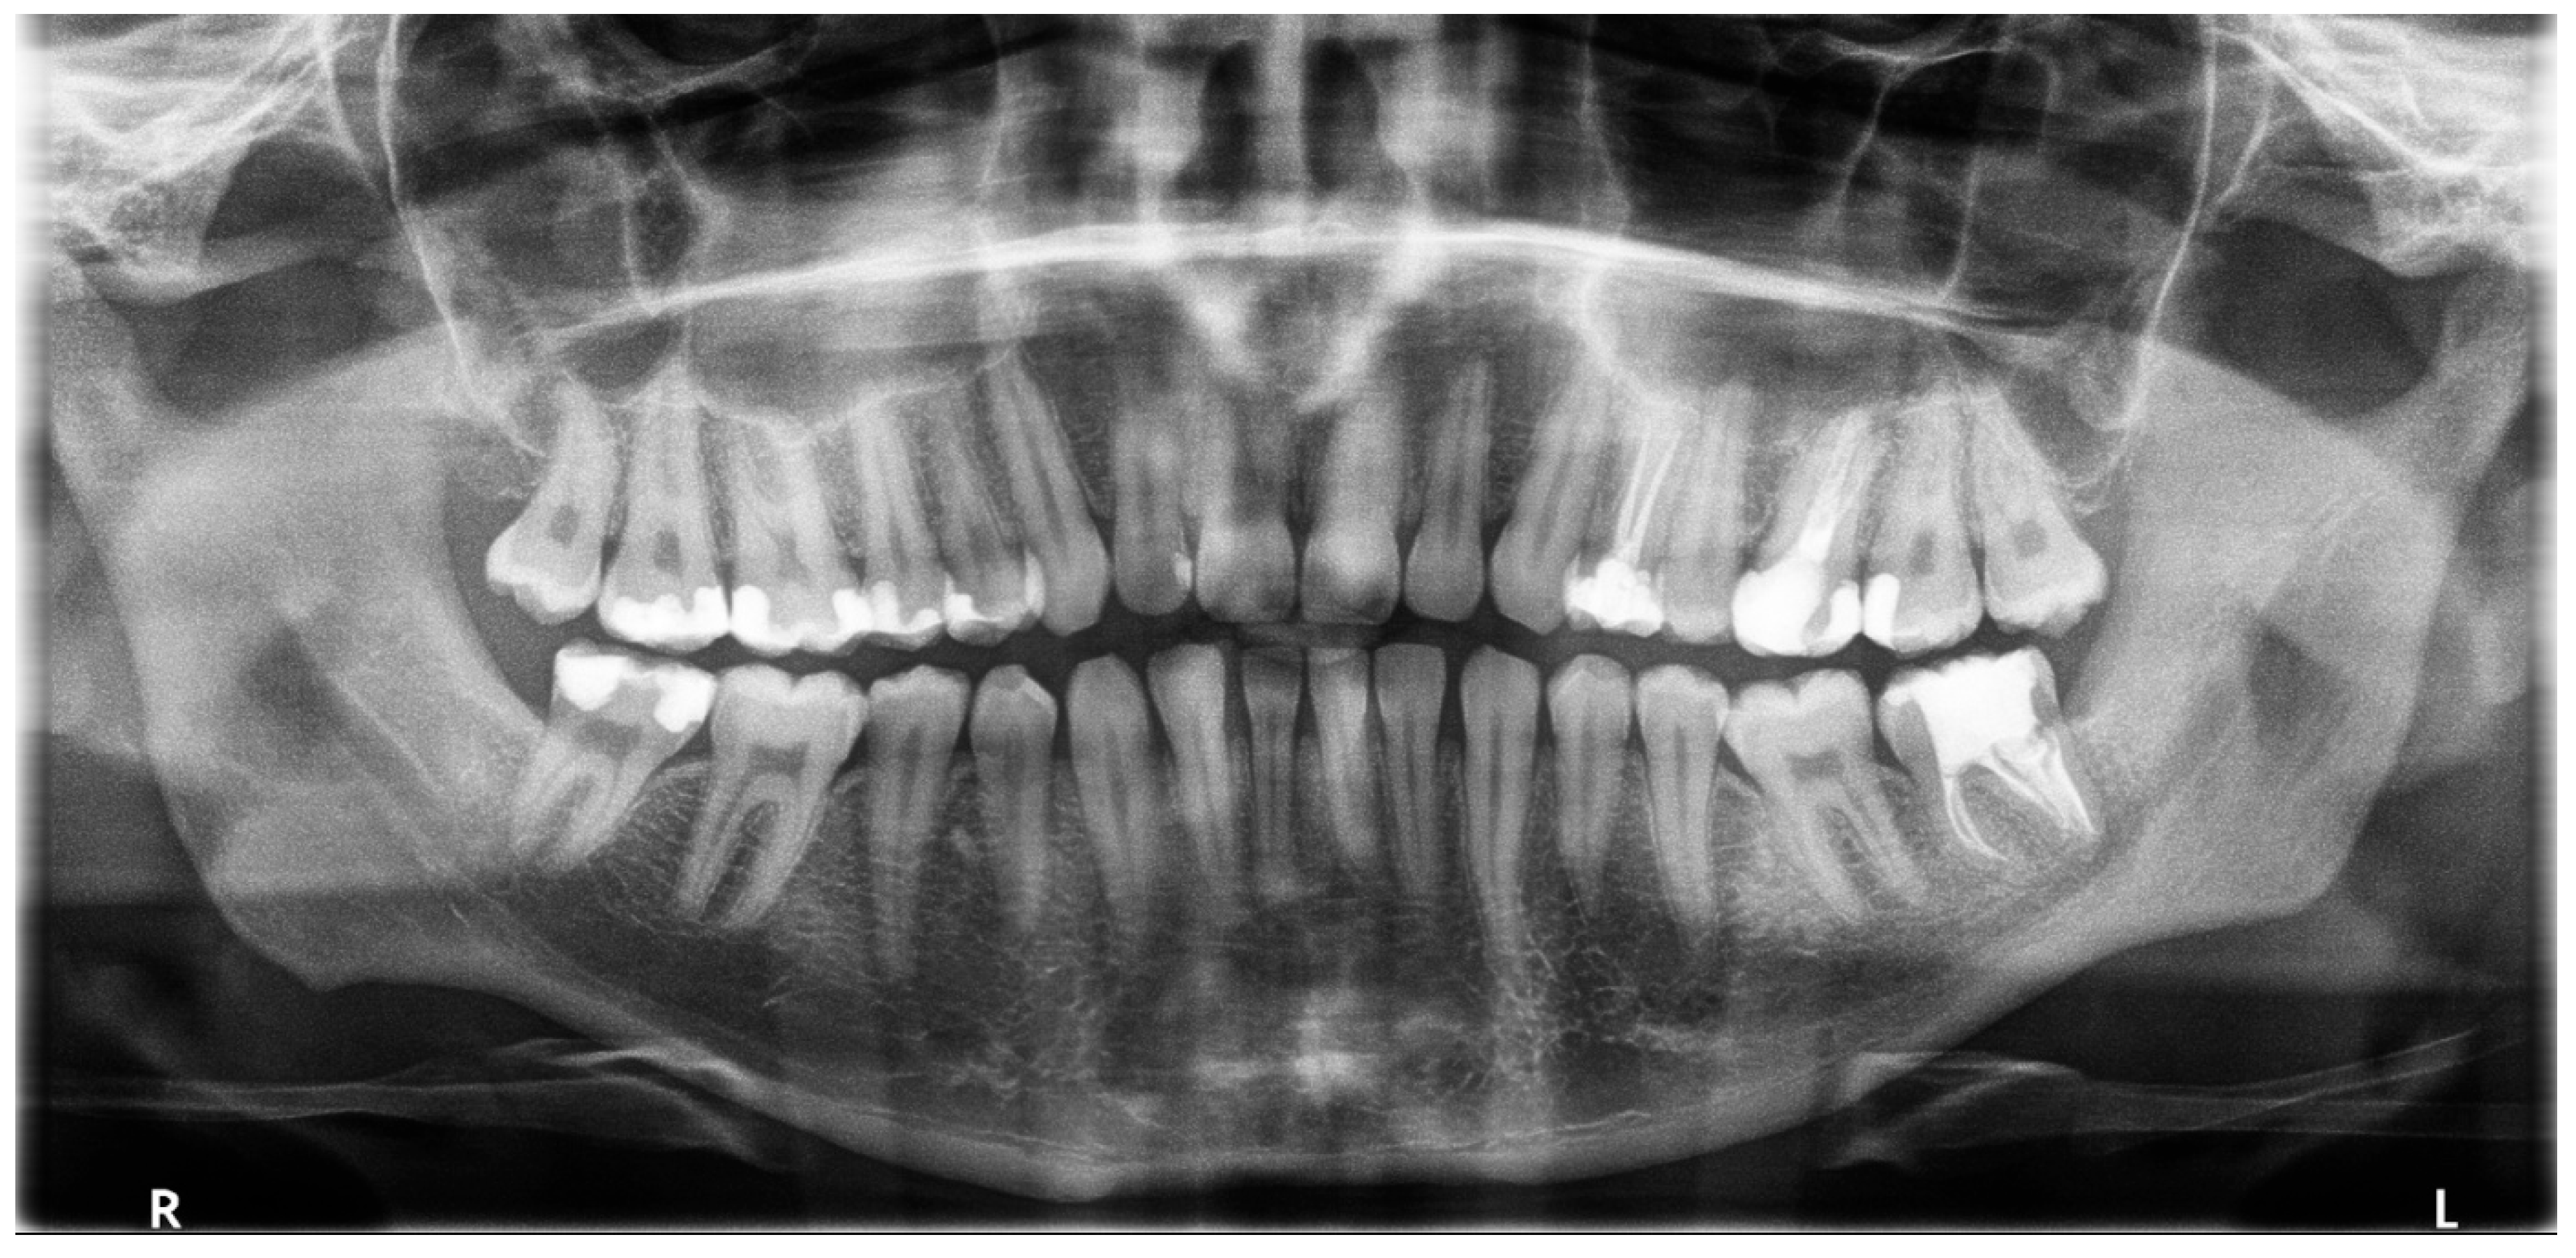

2. Case Presentation

2.1. The First Visit